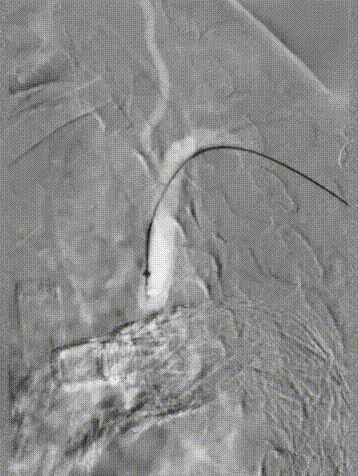

9. 进行主动脉弓部及头部造影,瘤体未见显影,双侧血流通畅,效果满意。

斑马导丝是治疗什么的「胸有乾坤」至简至易 行之有效—— Zone 0 TBE植入治疗弓部动脉瘤病例报道_https://www.jmylbn.com_新闻资讯_第24张

斑马导丝是治疗什么的「胸有乾坤」至简至易 行之有效—— Zone 0 TBE植入治疗弓部动脉瘤病例报道_https://www.jmylbn.com_新闻资讯_第25张